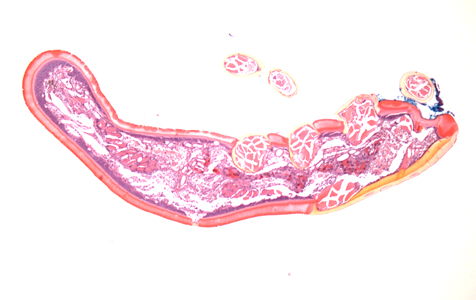

DPDx is an educational resource designed for health professionals and laboratory scientists. For an overview including prevention, control, and treatment visit www.cdc.gov/parasites/.